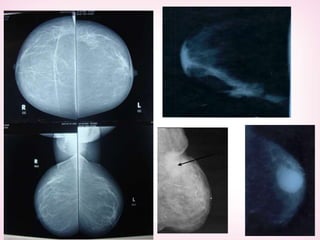

2- Radiology

1- Mammography

Def: low voltage compression X-ray taken in 2 directions

(craniocaudal—mediolateral)

Indication:

-female>35 - Doubtful mass - Nipple discharge-

--paget`s disease - Fllow up

ACCURACY: 90%